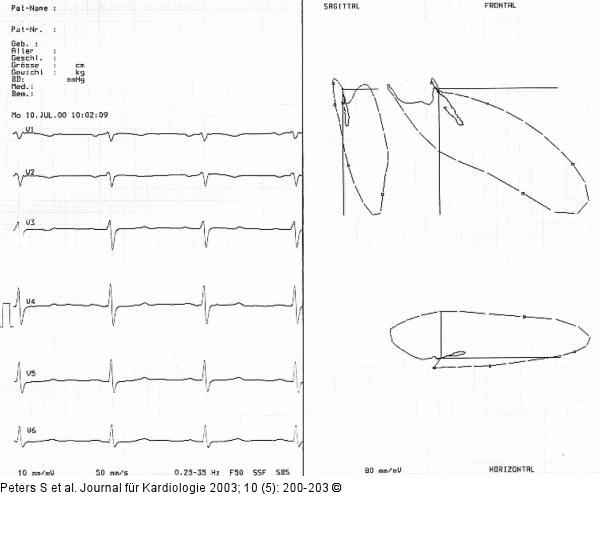

Abbildung 3: Vektorkardiographie Vektorkardiographie Beispiel 2 |